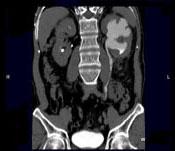

问题 男,58岁,尿频,尿痛伴低热乏力2月,CT如图所示,下列说法正确的是 ( )

选项 A、左侧输尿管结核 B、左侧输尿管癌 C、左侧输尿管多发性狭窄 D、左侧肾结核 E、左侧肾盂肾盏扩张,其边缘不整

答案 ACDE